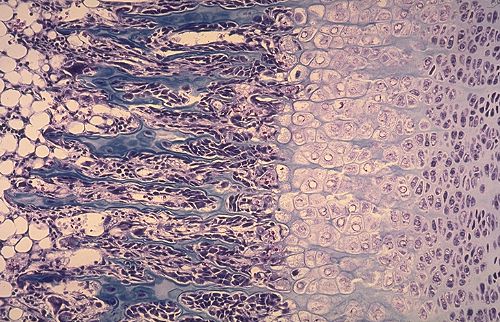

Avec la mise en place du centre primaire d'ossification, est que toutes les cellules de la régions diaphysaire vont s'hypertrophier?

Du coup, sous le facteur paracrine LHH qu'elles secrètent, si elles sont toutes hypertrophiées, le cartilage hyalin va être produit par les chondrocytes de l'épiphyse (car pas hypertrophiées)?